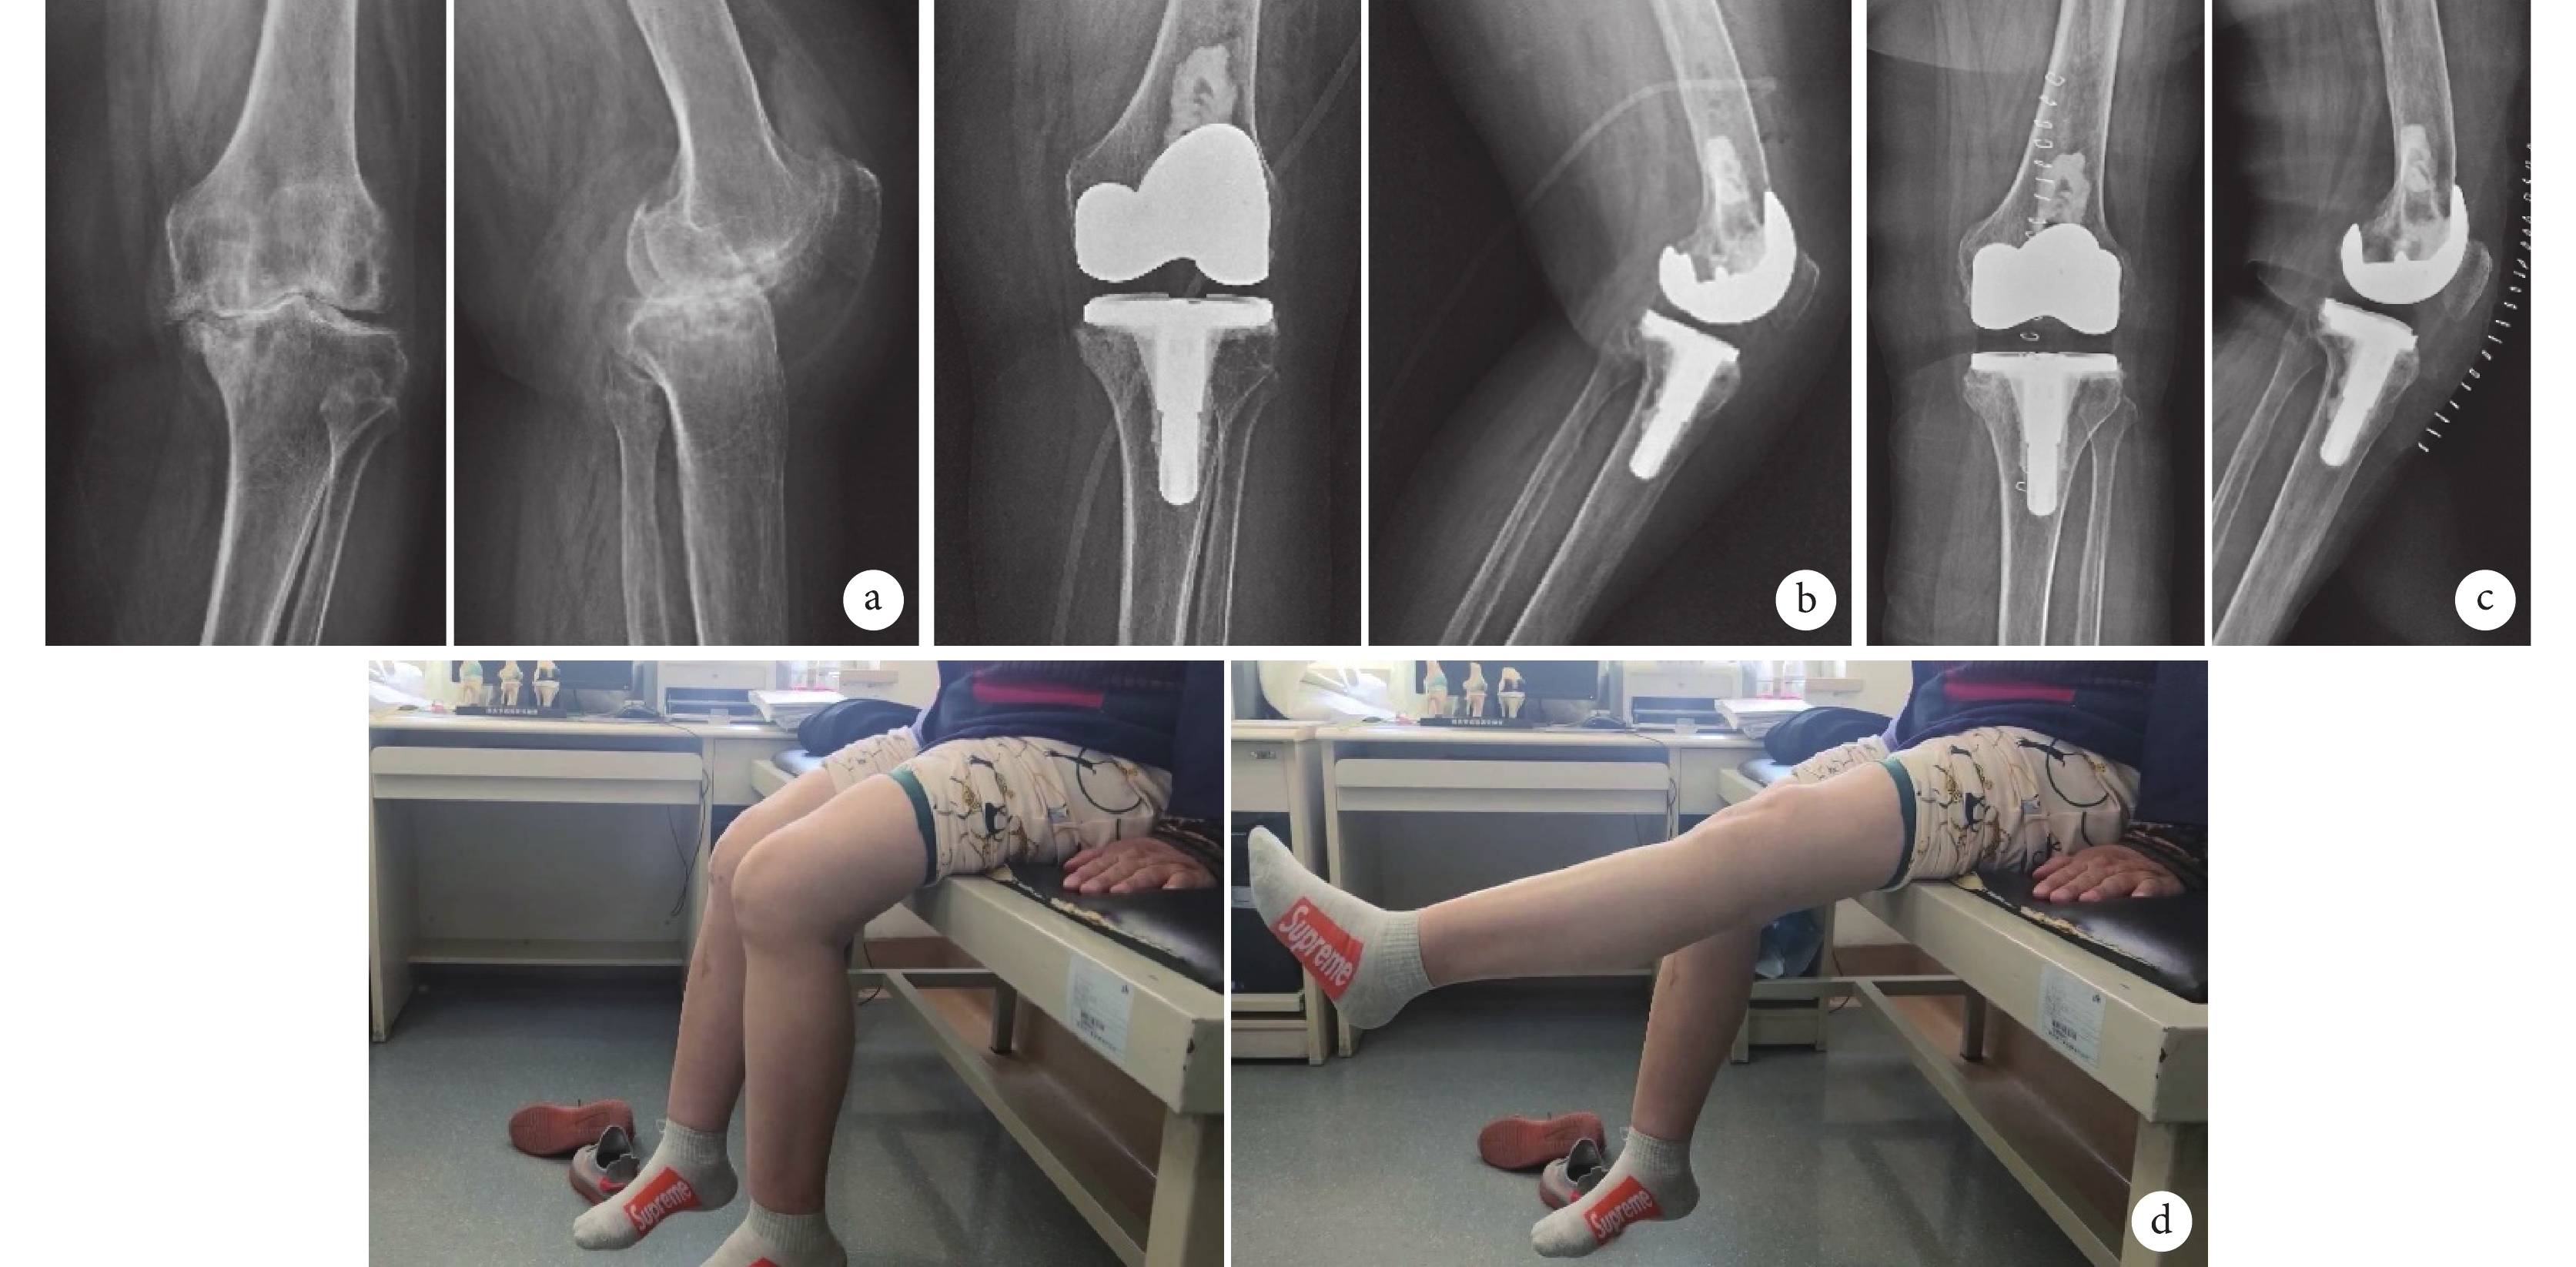

a. 術前正側位X線片;b. 術后3 d正側位X線片;c. TKA術后18個月翻修術后即刻正側位X線片;d. 翻修術后3年膝關節屈伸功能

Figure4. A 56-year-old female patient with osteoarthritis of right knee (Kellgren-Lawrence grading Ⅳ) in group B1a. Anteroposterior and lateral X-ray films before operation; b. Anteroposterior and lateral X-ray films at 3 days after operation; c. Anteroposterior and lateral X-ray films immediately after revision (at 18 months after TKA); d. Knee flexion and extension function at 3 years after revision

a. 術前正側位X線片;b. 術后3 d正側位X線片;c. 術后8個月正側位X線片;d. 術后4年膝關節屈伸功能

Figure3. A 62-year-old female patient with osteoarthritis of left knee (Kellgren-Lawrence grading Ⅳ) in group A1a. Anteroposterior and lateral X-ray films before operation; b. Anteroposterior and lateral X-ray films at 3 days after operation; c. Anteroposterior and lateral X-ray films at 8 months after operation; d. Knee flexion and extension function at 4 years after operation

末次隨訪時,A1、B1組間以及A2、B2組間β角、δ角、股脛角比較,差異均無統計學意義(P>0.05)。見表4。 膝關節X線透亮線評價示,A1、A2組各2膝術后即刻存在假體-骨界面透亮線,隨訪期間透亮線逐漸被新生骨填充,無新透亮線產生。B1、B2組術后即刻未發現透亮線,末次隨訪時2膝(B1、B2組各1膝)脛骨平臺假體存在假體-骨界面透亮線;各透亮線的寬度均<1 mm,在對應區域計1分,2膝假體綜合評分均≤4分,暫無透亮線增寬或假體松動現象。各組透亮線分布情況見表5。隨訪期間均無假體松動、下沉等并發癥發生。見圖3~6。